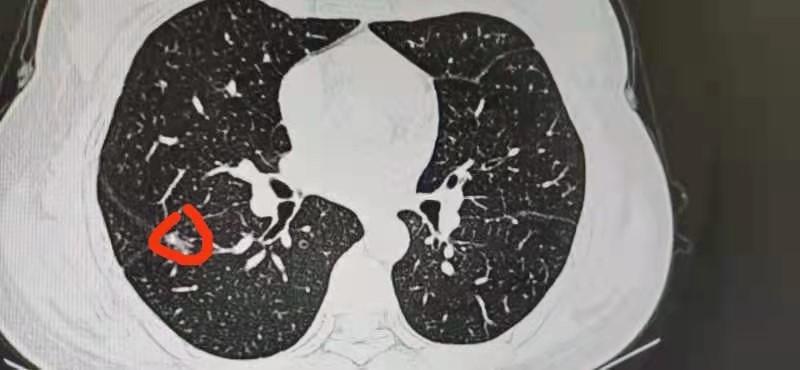

ct发现肺磨玻璃结节,怎么办?来听听影像医生怎么说!